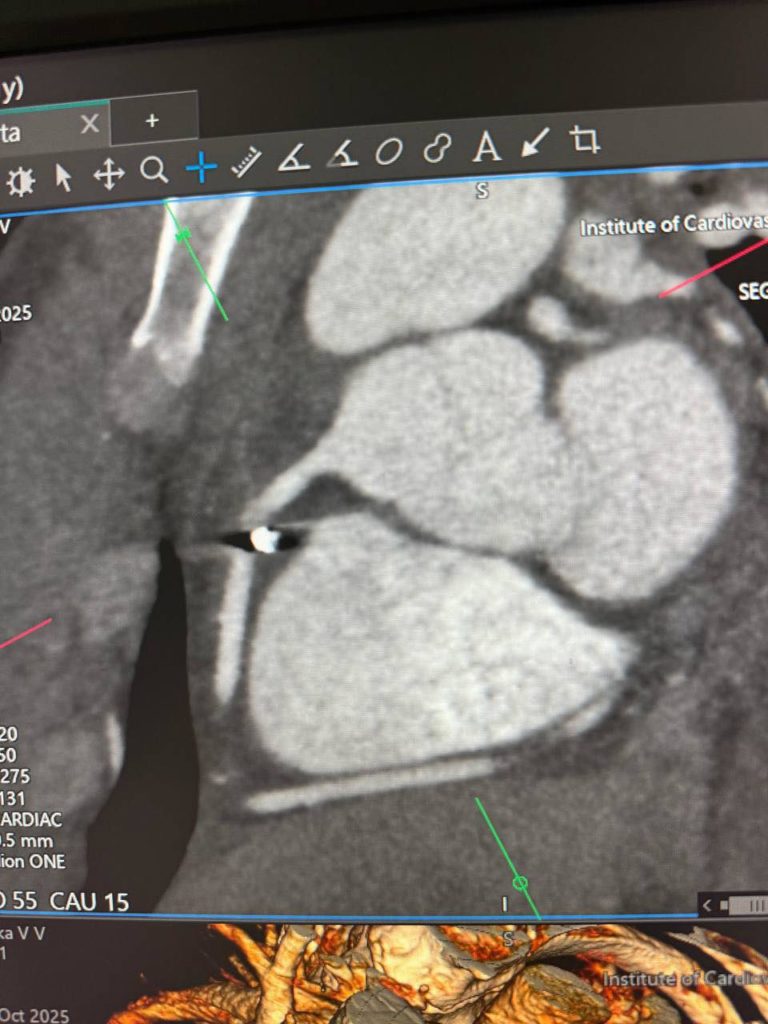

“Металевий уламок застряг у правій атріовентрикулярній борозні, біля правої коронарної артерії. Це надзвичайно небезпечна зона, де кожен рух може коштувати життя”, – розповіли медики.